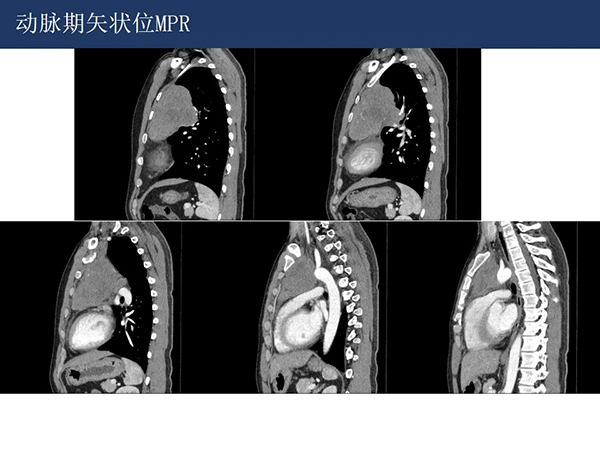

【院庆51周年】放射科:纵隔淋巴瘤